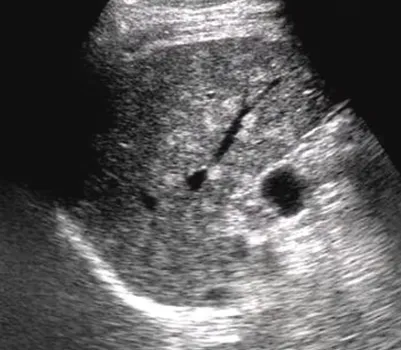

1.肝内单个或多个占位性病变。

2.早期呈低回声,边界不清,血流丰富。

3.脓液形成后,呈液性暗区,壁厚薄不均,内壁不平整,内透声差,可见絮状回声,有些可见分层。

4.肝脓肿进一步发展,内透声好,如肝囊肿,但壁厚薄不均。

5.后方结构(后壁)回声增强。